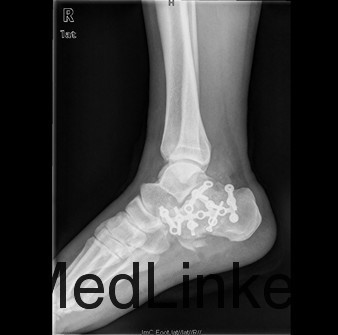

患者男,37岁,因“外伤后双足跟疼痛、肿胀伴腰痛11+天”入院。患者11+天前和工友施工时不慎从二楼摔下,双足跟着地,当时即感双足剧烈疼痛,踝关节活动障碍,伴腰背部疼痛,左足跟长约3厘米伤口,患者诉可见骨断端外露,伤后2小时患者被送往当地人民医院,急诊行清创缝合术,术后给予输液、抗炎、消肿等对症治疗,双足水肿减轻,患者为求诊治进一步诊治来我院,急诊以双足跟骨折收住我科。

查体:双足中度肿胀,左足跟底内侧长约3cm清创缝合术后伤口,伤口干燥,无红肿渗液,双足背、足底、双踝关节中度肿胀,双足皮温正常,足背动脉正常扪及,双下肢肌力五级,双足趾活动正常,双踝关节疼痛活动受限。 辅查:双足X线示:双足跟粉碎性骨折,关节面塌陷。

初步诊断:1、右跟骨粉碎性骨折2、左跟骨粉碎性开放性骨折清创缝合术后 诊疗计划:拟行双侧跟骨切开复位植骨、钢板、螺钉内固定术+髂骨取骨术